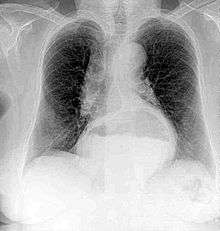

A chest radiograph of a female, demonstrating a hiatus hernia

Since Röntgen's discovery that X-rays can identify bone structures, X-rays have been used for medical imaging. The first medical use was less than a month after his paper on the subject.[22] Up until 2010, 5 billion medical imaging studies have been conducted worldwide.[23] Radiation exposure from medical imaging in 2006 made up about 50% of total ionizing radiation exposure in the United States.[24]

A radiograph is an X-ray image obtained by placing a part of the patient in front of an X-ray detector and then illuminating it with a short X-ray pulse. Bones contain much calcium, which due to its relatively high atomic number absorbs x-rays efficiently. This reduces the amount of X-rays reaching the detector in the shadow of the bones, making them clearly visible on the radiograph. The lungs and trapped gas also show up clearly because of lower absorption compared to tissue, while differences between tissue types are harder to see.

Radiographs are useful in the detection of pathology of the skeletal system as well as for detecting some disease processes in soft tissue. Some notable examples are the very common chest X-ray, which can be used to identify lung diseases such as pneumonia, lung cancer, or pulmonary edema, and the abdominal x-ray, which can detect bowel (or intestinal) obstruction, free air (from visceral perforations) and free fluid (in ascites). X-rays may also be used to detect pathology such as gallstones (which are rarely radiopaque) or kidney stones which are often (but not always) visible. Traditional plain X-rays are less useful in the imaging of soft tissues such as the brain or muscle.